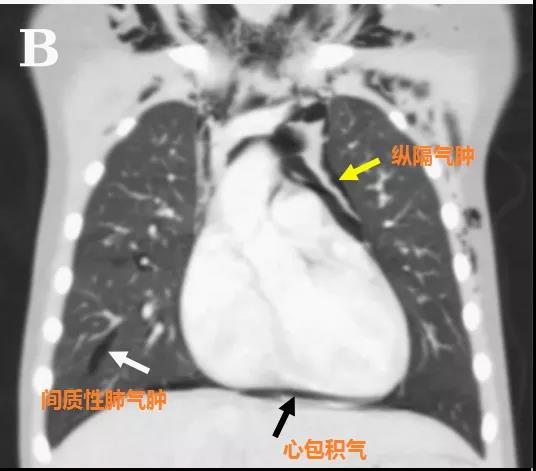

頭顱、胸部CT提示廣泛皮下氣腫、縱隔氣腫、心包積氣、甚至眼眶周圍都積氣,眼球突出!頸部無感染征象,腸管無破裂征象,看來氣體還是來自肺部。但是,肺部無感染、無肺大泡、無劇烈咳嗽,只有間質性肺氣腫。縱隔氣腫、皮下氣腫的治療,核心是根除病因,切開引流效果不像氣胸那么理想,而且縱隔切開引流還存在手術風險。找不到病因,如何是好?考慮患者是過敏體質,有皮疹,繼續呼吸機輔助呼吸,先治療過敏,肌肉注射腎上腺素、靜脈注射類固醇激素和抗組胺藥、吸入支氣管擴張劑等。經上述治療,臨床表現和影像學方面都有迅速的改善。隨后拔出氣管導管,口服類固醇激素出院,門診隨訪。